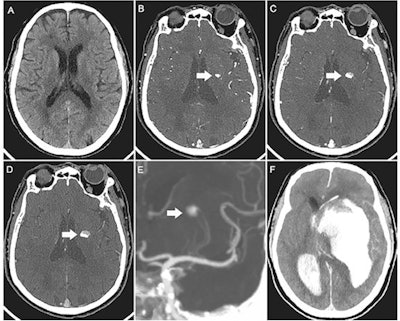

Images of a 15-year-old boy with myocarditis after COVID-19 vaccination. One day after receiving his second vaccination dose, he developed fever, myalgia, and intermittent tachycardia. (A) T2-weighted short inversion time inversion recovery MRI scan at 1.5 T in short-axis view shows focal high-signal intensities (arrow) at basal lateral and inferior wall, indicating myocardial edema. (B) Late gadolinium enhancement image in short-axis view shows corresponding linear subepicardial enhancement (arrow), indicating inflammatory myocardial necrosis. (C) T1 mapping and (D) T2 mapping in short-axis view show elevated T1 and T2 at the midventricular lateral and inferolateral wall (arrow in C and D), indicating acute myocardial injury (focal T1, 1165 msec; focal T2, 70 msec; institution-specific cutoff values for acute myocarditis: T1 global ≥1000 msec, T2 global ≥55.9 msec).The second runner-up was a tie between two articles. The first, "CT of Ongoing Intracerebral Hemorrhage," is by a group at the People's Hospital of Deyang City in Sichuan, China. The image captured the rapid evolution of a progressively expanding intracerebral hemorrhage in a 73-year-old man.

Images of a 73-year-old man with acute left-sided weakness. (A) Axial noncontrast CT image of the head shows no intracerebral hemorrhage. (B) Arterial phase CT angiogram obtained 192 seconds later, after administration of contrast material, demonstrates focal enhancement in the left basal ganglia (arrow). (C, D) CT angiograms obtained in the (C) second and (D) third phases, with delays of 39 seconds and 38 seconds, respectively, highlight the active expansion of the intracerebral hemorrhage with the blood-contrast level (arrows). (E) Coronal maximum intensity projection image reveals that the bleeding was located near the distal ends of the lenticulostriate arteries (arrow). (F) Follow-up noncontrast CT image obtained 1 hour after the third phase CT angiogram shows massive enlargement of the hematoma, intraventricular hemorrhage, hydrocephalus, and subfalcine herniation.All three images exemplify the significant contributions made by radiology to the field of medicine and were selected from 43 images published between 2 July 2021 and 30 June 2022, up from 29 in 2021, the journal said.